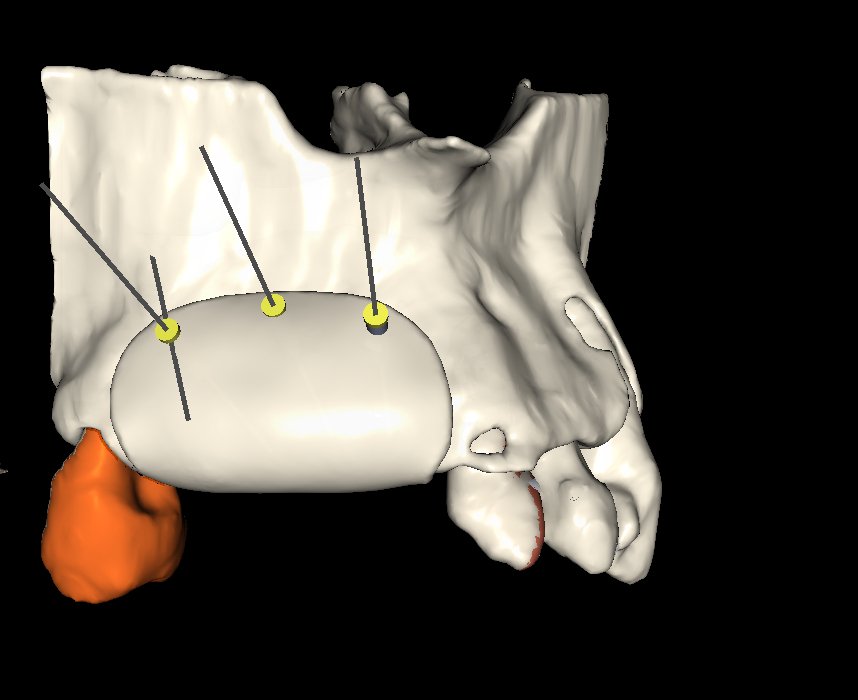

• Concepto de barrera personalizada.

• Principios de diseño biomecánico.

• Espesor, extensión y bordes de la barrera.

• Diseño pasivo y adaptación milimétrica.

• Planificación de tornillos de fijación:

• Número

• Posición

• Angulación

• Relación barrera hueso – tejidos blandos.

• Control de calidad del diseño final.

• Ajustes prequirúrgicos.